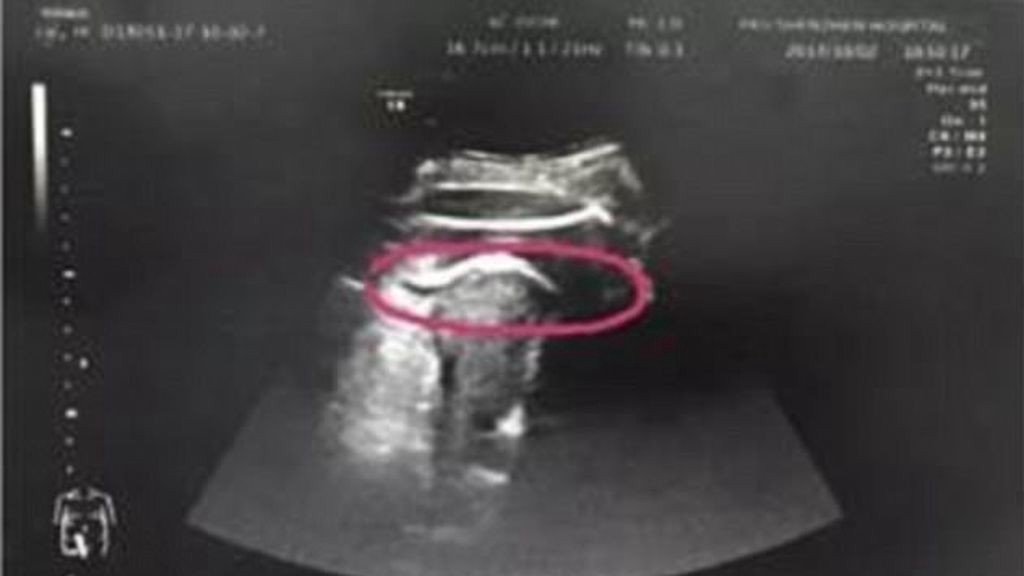

El Hospital de Shenzhen de la Universidad de Pekín ha trasmitido en un comunicado que la mujer ingresó con un fuerte dolor abdominal. Después de una ecografía, los médicos observaron una de las piernas de la niña fuera del vientre de la madre.

Los médicos vieron que la ruptura, de 7 centímetros de largo, coincidía con la cicatriz de la intervención anterior. Después de que el bebé la abriese de una patada, el líquido amniótico se salió y la mujer tuvo que ser operada de urgencia.